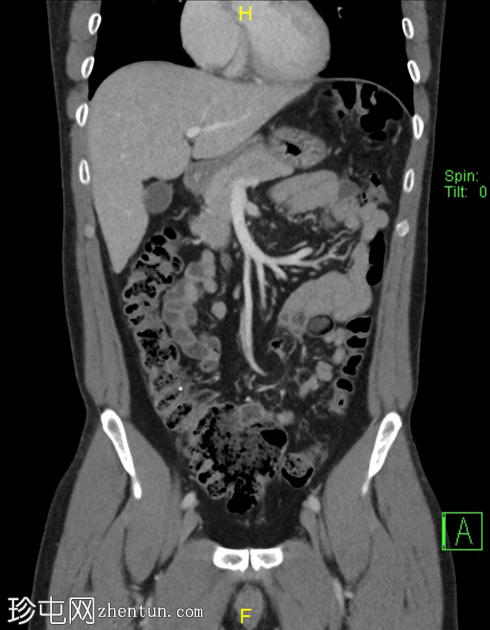

轴位增强扫描(门静脉期)

冠状位增强扫描(门静脉期)

盲肠位于盆腔正中,充满粪便。回盲瓣位于正中。未见明显炎症改变。